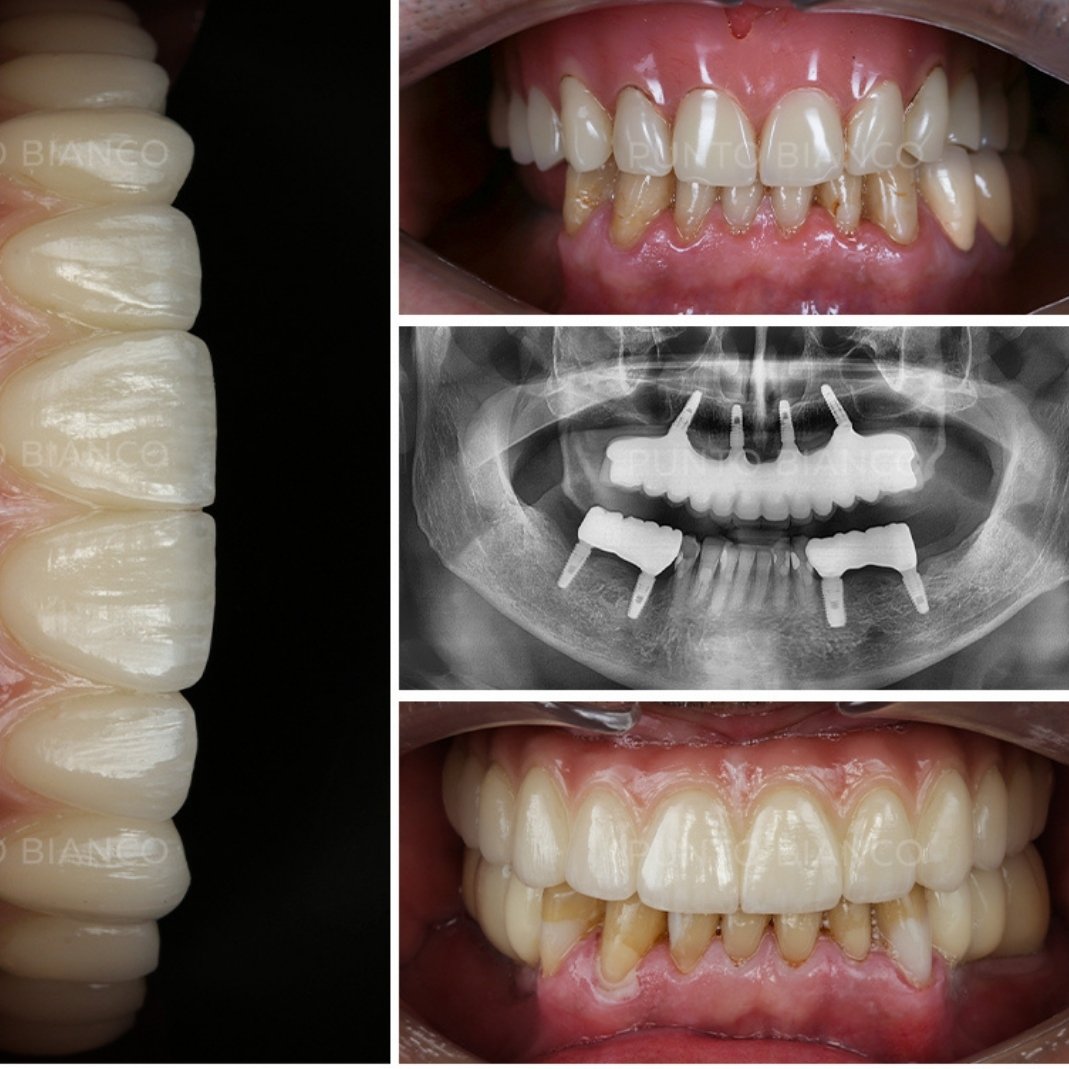

Protezele dentare fixe pe implanturi sunt concepute pentru a semăna cât mai mult cu dinții naturali, atât din punct de vedere estetic, cât și funcțional. Iată câteva aspecte cheie ale acestora:

Unul dintre avantajele majore ale protezelor fixe pe implanturi este procesul de osteointegrare, prin care implanturile dentare fuzionează complet cu osul maxilar sau mandibular. Această integrare oferă o bază stabilă și durabilă pentru proteză, prevenind pierderea de masă osoasă care poate apărea în cazul dinților absenți. Pe lângă aspectul și funcționalitatea naturală, osteointegrarea contribuie la sănătatea pe termen lung a structurii osoase și a cavității bucale, menținând conturul facial și prevenind modificările fizionomiei cauzate de resorbția osului.